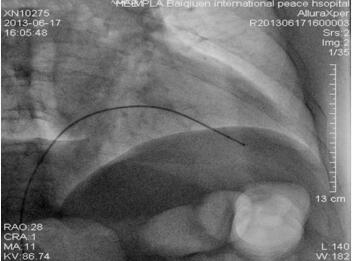

给予盐酸替罗非班静脉泵入,RCA植入支架(2.5mm × 23mm Xience V支架),血流恢复(图1-23-5)。冠状动脉造影及支架手术顺利,患者胸闷症状缓解。术后12小时出现间断起搏不良,床旁非透视下微调起搏电极后起搏功能恢复正常。术后24小时再次出现起搏功能不良,导管室透视下与前一天临时起搏电极位置(图1-23-6)比较,发现心室起搏电极头端在右室心尖部较前有移位,位置较深(图1-23-7),遂撤出电极导线将起搏电极导线重新调整定位,起搏感知功能良好,起搏频率50次/分,观察血压正常,回到监护病房。

图1-23-7 临时起搏电极位置(较急诊影像比较临时起搏器电极头端向前移位)